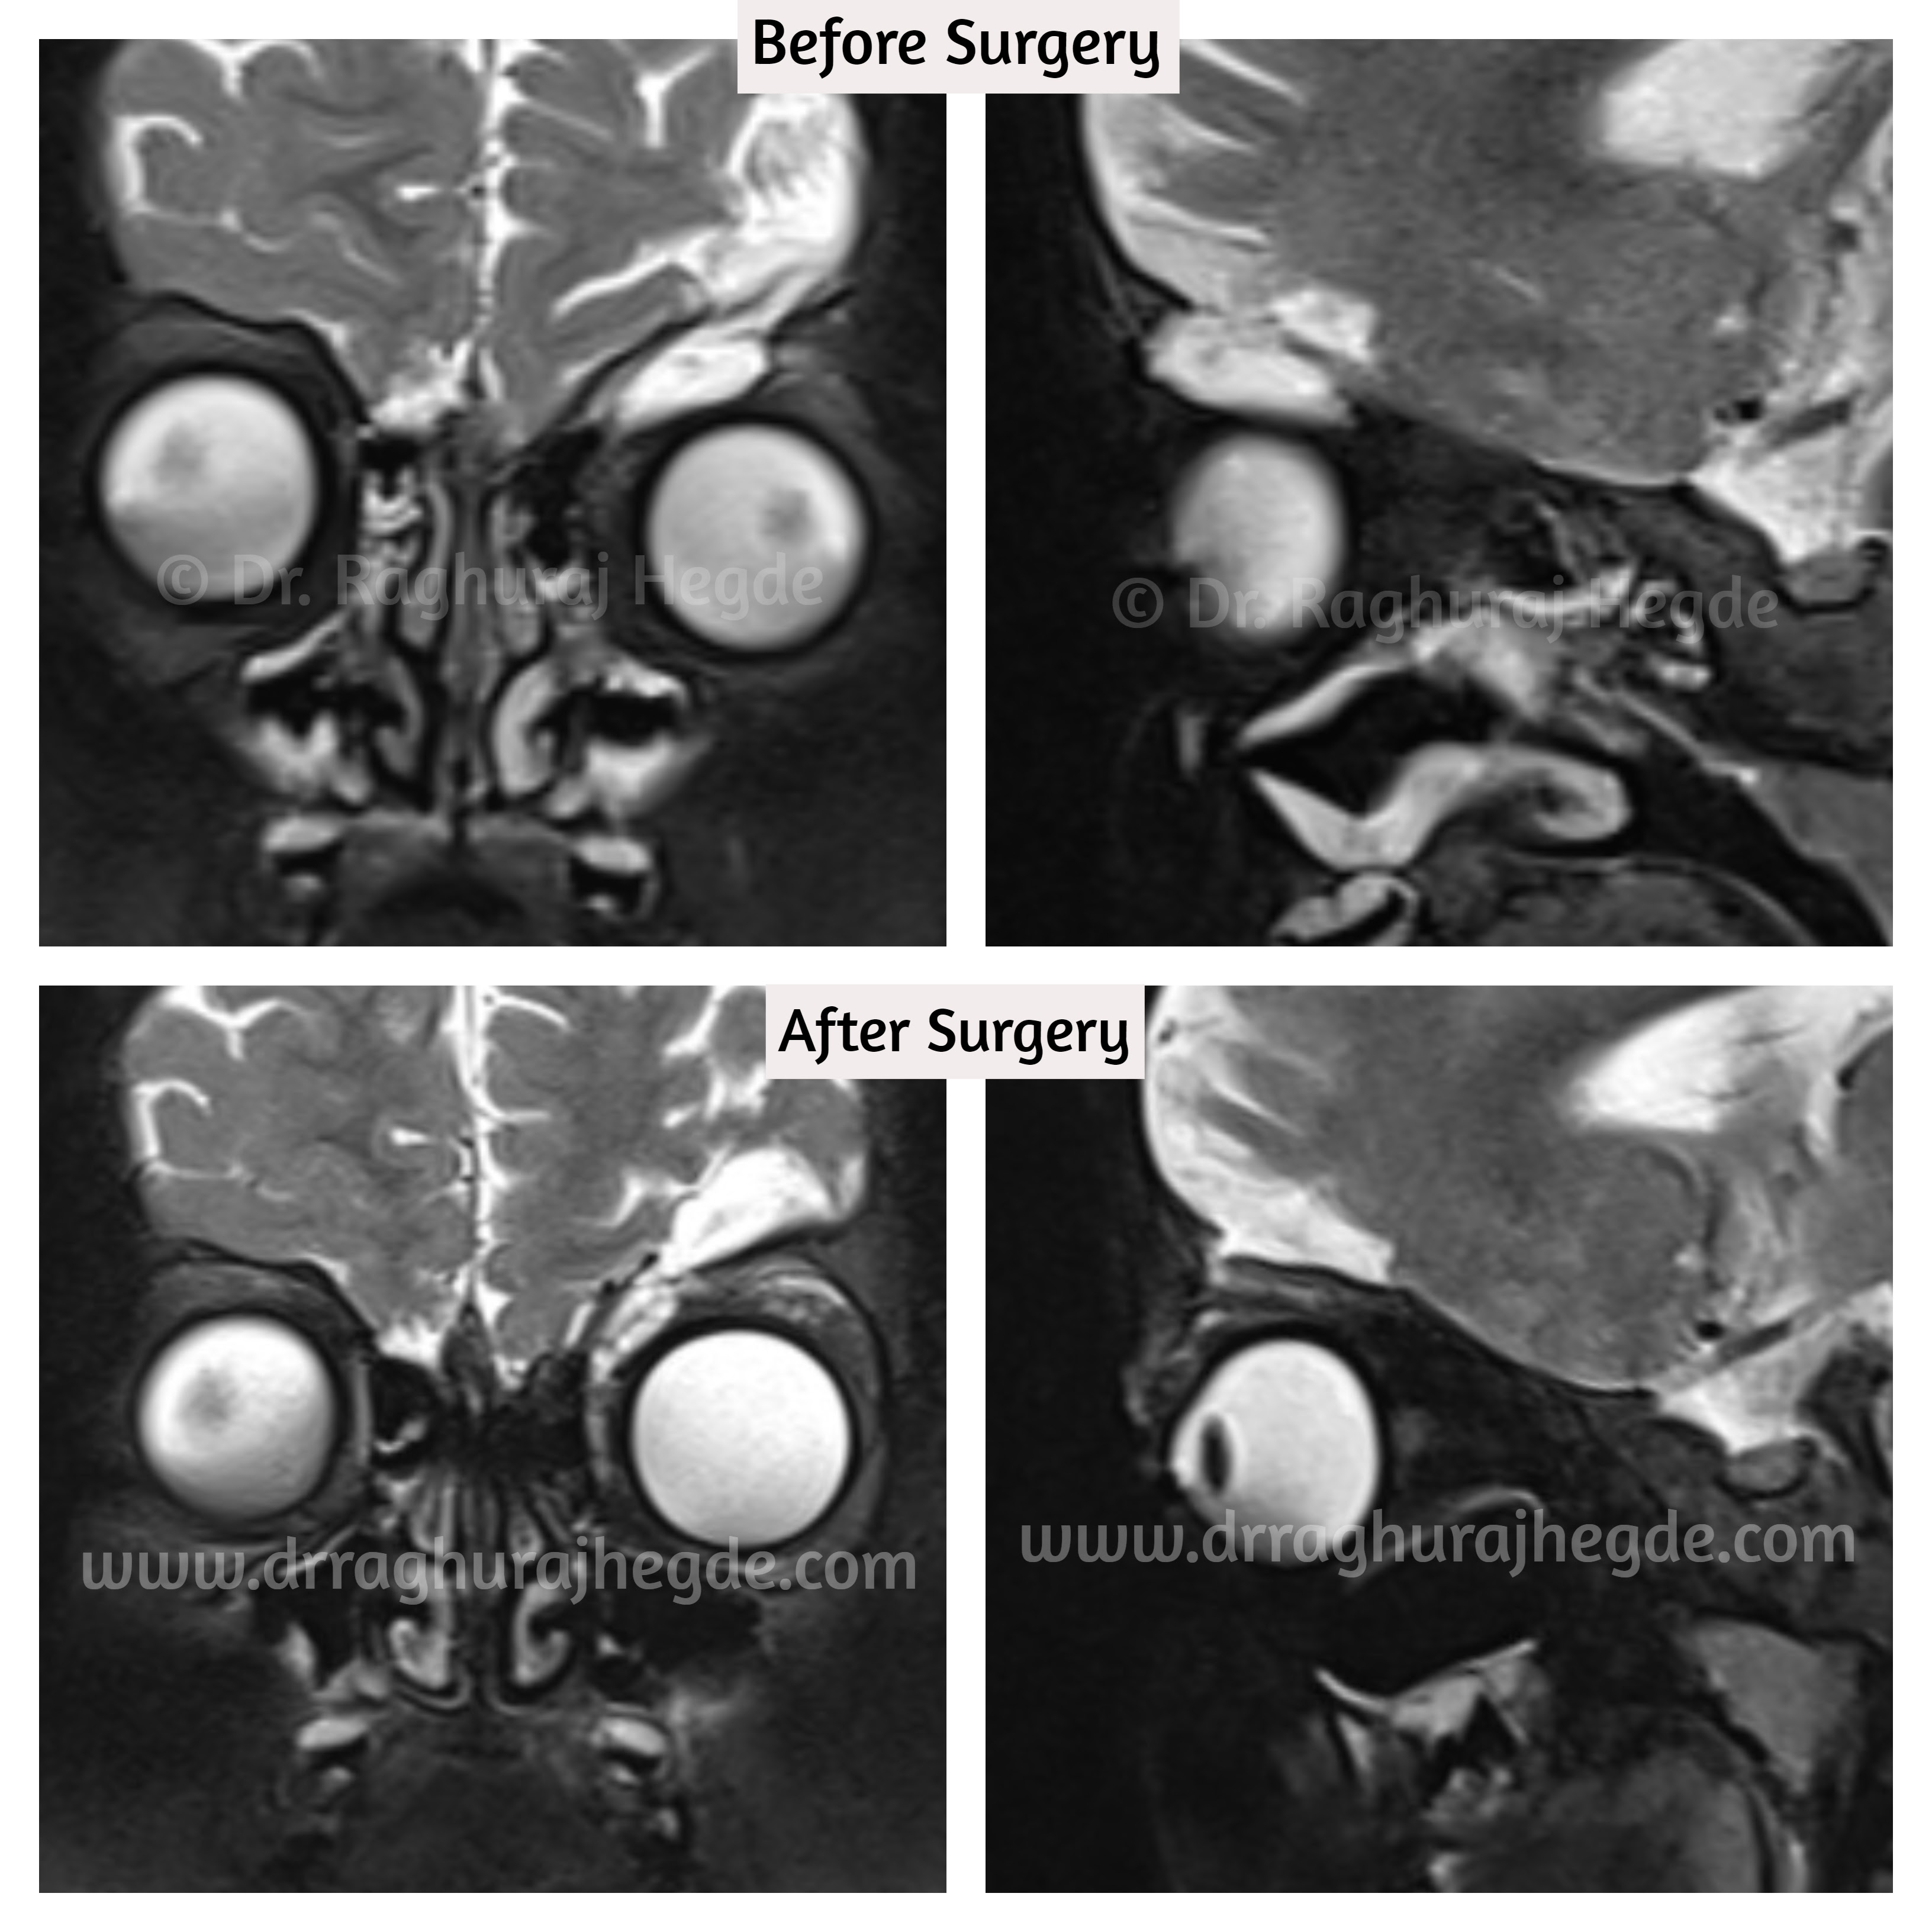

Wanted to update this case with post operative outcome and imaging photos.

About 8 weeks out from surgery, the child is doing well. The CSF Rhinorrhoea, headaches and hypoglobus has resolved. The sub-cutaneous emphysema has about 90% resolved and only the nasal area is getting filled up and not much of a problem. She has Left orbital residual enophthalmos resulting in left Pseudo-ptosis.

The post operative MRI imaging reveals that roof defect repair is successful and there is no proplapse of intra-cranial contents to the left orbit anymore.

As of now, we have decided not to chase after the left orbital enophthalmos and ptosis and wait for the tissues to recover from surgery. We will probably revisit the residual conditions at a later date.